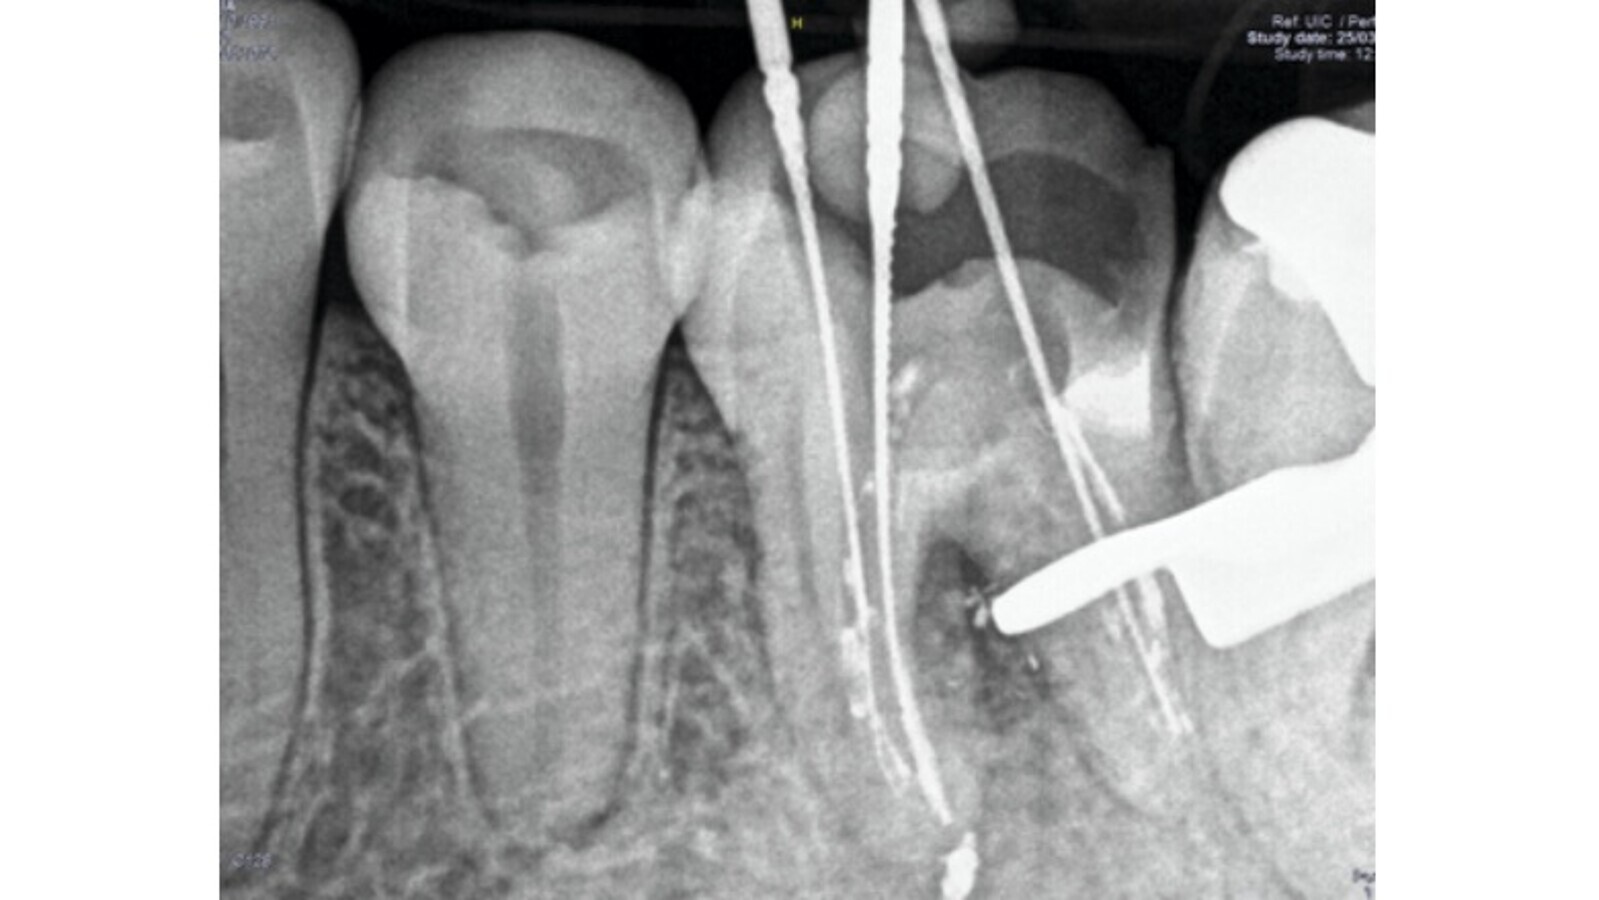

guardar

Fig. 6. Remoción de la gutapercha y localización de la longitud de trabajo.